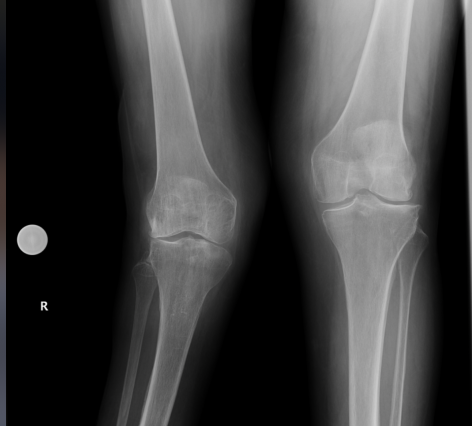

In 1950, I got polio when I was 18 months old. I was fortunate that I wasn’t left paralyzed. It weakened and atrophied my right leg. By my late 50s I began to experience progressing weakness and more problems with my right leg. My foot was turning over, while my knee was valgus and losing stability. I had arthroscopic knee surgery in 2005, and then a foot fusion in 2014. However, neither stopped the deterioration and increasing instability of my leg. By 2006 I was diagnosed with Post-polio syndrome (PPS). The past two years this worsened and even with a knee-ankle-foot orthosis (KAFO), my leg was hyperextending and buckling in every direction, with the knee dipping sideways and backward constantly.

I consulted a top knee surgeon in North Carolina, but he said I was not a good candidate for regular knee replacement nor a hinged knee replacement. When we visited New York last December, I was lucky to get a last minute appointment with Dr. Shen. He thoughtfully evaluated my x-rays, history and present condition. He said he felt a hinge knee replacement would help me. He said he would meet in January with a panel of doctors who review complex cases and let me know their recommendations. After this meeting, we had a virtual appointment, where he said the panel felt a hinged knee replacement would best address my problems. I was very hesitant and concerned about complications. Dr. Shen listened and responded to all my questions and anxiety with consideration and empathy.